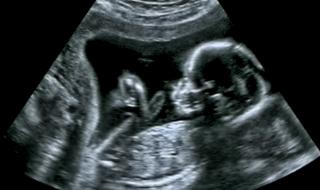

Генетична мистерия e причината за 1/2 от всички нарушения в развитието на плодаВъпросът, който вълнува всеки родител е дали нероденото им дете ще има някакво смущение в развитието си, но изглежда, че засега отговорът на този в ...11.11.20186 4052 -